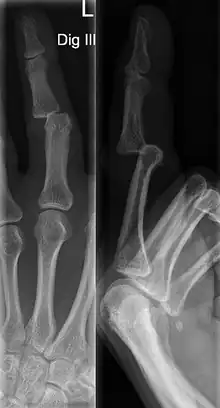

Dislocations can be categorised based on location and type. The finger can be split into three bones and two joints in an alternating order. From the fingertip to the knuckle, these are as follows; distal phalanx, distal inter-phalangeal (DIP) joint, middle phalanx, proximal inter-phalangeal (PIP) joint, and proximal phalanx. DIP dislocations are much less common than PIP dislocations,[2] due to the "stability provided by strong collateral ligaments, palmar plates, and tendinous insertions, as well as the short lever arm of the distal phalanx".[7] Dislocations can be categorised based on the direction that the fingertip moves in relation to the knuckle, be it in the direction of the palm (volar dislocation), or the direction of the back of the hand (dorsal dislocation). Of the two, dorsal dislocations are more common.[3] If reduction has been attempted, an x-ray of the dislocation should appear concentric if successful.[2] However, if there is a fracture present, there will be a misalignment of the joint, which will be evident from the radiograph.[2] Bach suggests a referral to a hand surgeon if a misalignment is present.[2]

Fractures are instances where the bone's structural integrity has been compromised. This is indicated by midshaft pain, as well as visual midshaft angulation or rotation.[3] As with any skeletal injury, an x-ray can be conducted to verify the presence of a fracture.[1] The distal phalanx is especially vulnerable to avulsion fractures, where a fragment of bone is ripped off when the tendon separates from the phalanx.[1] Avulsion fractures are especially common following a first time dislocation.[1] These are especially concerning, as it may indicate a complete tear of the extensor digitorum tendon. If left untreated, this may lead to permanent DIP extensor lag (inability to fully straighten the finger).[8]

DIP Dislocation

PIP Dislocation